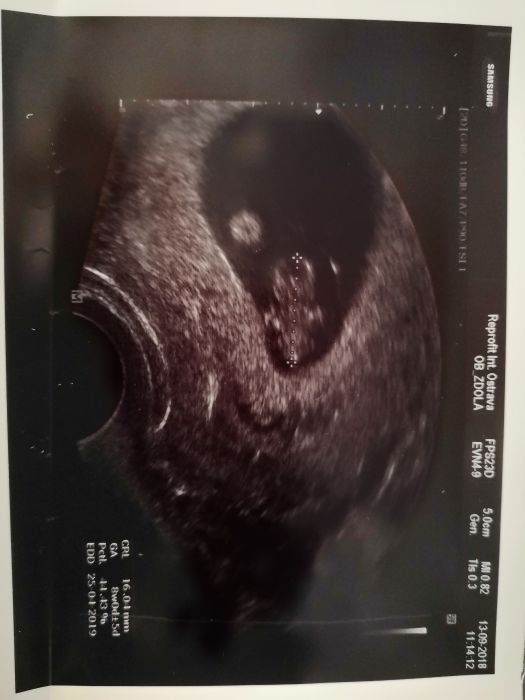

Tak holky podle MS jsem v 7tt ale kinder vajicko odpovídá 8 tt. Za 2 týdny jdu na kontrolu a dostanu průkazku :) TP podle MS 2.5 ale doktor říkal že mám počítat konec dubna. Jinak už se hybe a dostala jsem 3 fotky :)

Ted se dívám na ultrazvuk a ta druhá tečka je asi placenta,že? U malého jsem první fotku měla až ve 3 měsíci tak vůbec nevím. Dekuji

Ahoj holky, ráda bych se k Vám také přidala, jestli můžu :-) Jinak Mišpule, neboj, ta druhá tečka je žloutkový váček, který vyživuje miminko, než se právě vytvoří placenta